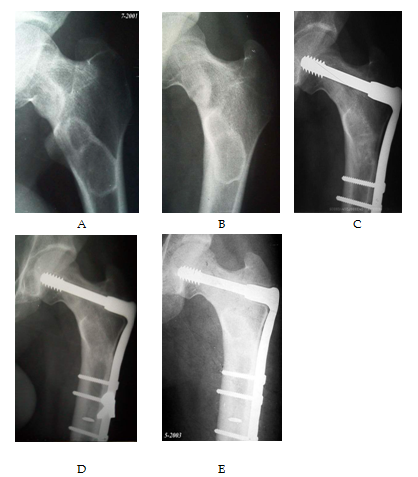

Excluded from this study any patient who already developed pathological fracture. Different types of fixation either surface plating (dynamic hip screws) (Figure 3 & 4) medullary (Gamma nails) (Figure 5) or external fixation in cases unsuitable for surgery (Figure 6) were used according to the type and the site of the deformity. In tibial cases, we used the tourniquet without blood evacuation in the limb.

Figure 3 Preoperative X –ray with osteolytic lesion at upper end femurs A and B. The lesions are greater than diameter of bone on maximum dimension and in high risk fractures. This defect of the femur will cause significant decrease in the mechanical performance of the femur when resisting external load and twisting. C and D show immediate postoperative prophylactic fixation by dynamic hip screws and bone grafting. E and F show follow up after 2 years with complete incorporation of the graft.